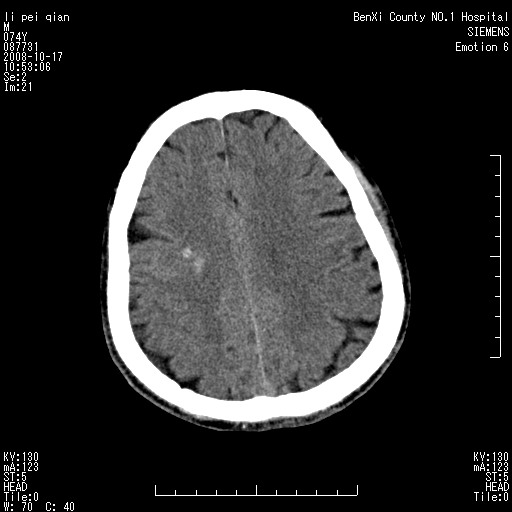

以下是引用影像孺子牛在2008-10-17 11:31:00的发言:[br]考虑:钙化。其一为病变密度特别高,其二如为出血其周围应有水肿带。